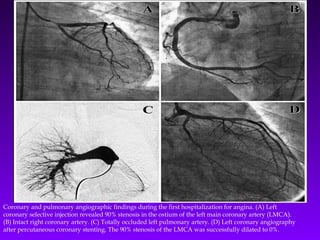

Coronary and pulmonary angiographic findings during the first hospitalization for angina. (A) Left

coronary selective injection revealed 90% stenosis in the ostium of the left main coronary artery (LMCA).

(B) Intact right coronary artery. (C) Totally occluded left pulmonary artery. (D) Left coronary angiography

after percutaneous coronary stenting. The 90% stenosis of the LMCA was successfully dilated to 0%.

Coronary and pulmonaryangiographic findings during the first hospitalization for angina. (A) Left coronary selective injection revealed 90% stenosis in the ostium of the left main coronary artery (LMCA). (B) Intact right coronary artery. (C) Totally occluded left pulmonary artery. (D) Left coronary angiography after percutaneous coronary stenting. The 90% stenosis of the LMCA was successfully dilated to 0%.